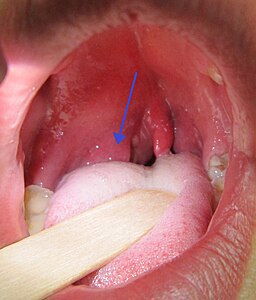

Background: Patients will present with unilateral throat pain, trismus and often have a muffled quality to their voice (“hot potato” voice). On examination, trismus may be evident and it may make visualising the back of the throat difficult. If the back of the throat is visible, there is often a bulge in the tissue of the soft palate just above the tonsil. This can cause uvular deviation to the opposite side. However, it is important to note that deviation of the uvula describes the base of the uvula off the midline, rather than its tip which can occasionally stick to the wall of the throat temporarily. In addition, the presence of unilateral throat pain and trismus are more predictive for the diagnosis of quinsy compared to uvular deviation. Therefore, if there is no unilateral throat pain and no trismus, the diagnosis of quinsy is very unlikely.

James Heilman,MD, CC BY-SA 3.0 https://creativecommons.org/licenses/by-sa/3.0, via Wikimedia Commons https://commons.wikimedia.org/wiki/File:PeritonsilarAbsess.jpg